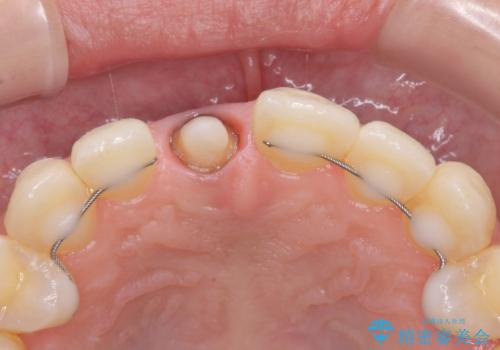

ファイバーコアにやり替えて、形を整え直して、

精度の高いシリコーンで型どりしました。